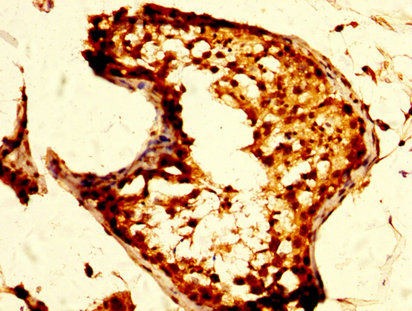

IHC image of CSB-PA016361LA01HU diluted at 1:500 and staining in paraffin-embedded human testis tissue performed on a Leica BondTM system. After dewaxing and hydration, antigen retrieval was mediated by high pressure in a citrate buffer (pH 6.0). Section was blocked with 10% normal goat serum 30min at RT. Then primary antibody (1% BSA) was incubated at 4°C overnight. The primary is detected by a biotinylated secondary antibody and visualized using an HRP conjugated SP system.